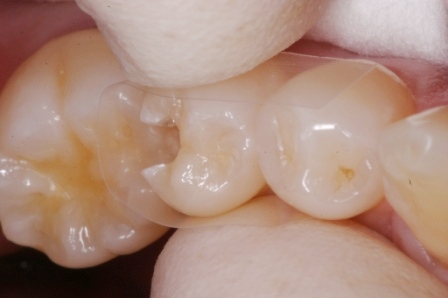

虫歯は金属の錆や腐食と同じ1.42 2025.11.10

虫歯は金属の錆や腐食と同じ1.41 2025.06.05